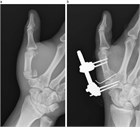

1. 骨折する部位により特徴的な変形を呈する。

1. 関節拘縮を起こさないような内固定と外固定が必要であり、解剖の熟知が重要である。